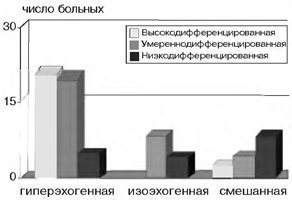

Változékonyság ultrahangos kép méhnyálkahártya rák miatt jelentősen mérete és a differenciálódását.

Azt találtuk, hogy csak akkor, ha az összeg a M-echo 1,5 cm hyperechoic szerkezete továbbra is, egy a tumorméret növekedése legfeljebb 2 cm vagy több, úgy válik egyre heterogén, mind meghatározva szabálytalan visszaverődés növekedett, és a közepes és alacsony intenzitású. Amikor a tumor mérete több mint 3 cm, és a vegyes izoehogennoe érvényesülnek, „foltos” szerkezet.

Következésképpen, egy a tumorméret növekedése megnövekedett heterogenitása ultrahangos kép endometriális rák.

Azt is nyomon követhető egyértelmű függését az ultrahang leképezés jellegét a méh rákos test morfológiai típusát.

A függőség az ultrahangos kép endometriális rák által morfológiai variáns tumor

Tanulmányunkban, a magas és közepesen differenciált adenocarcinoma jellemezve hyperechoic szerkezetét, míg a specifikus volt csak, hogy az tükrözze a közepes és alacsony intenzitású, hogy az alacsony minőségű rák, nem egységes, vegyes szerkezetű.